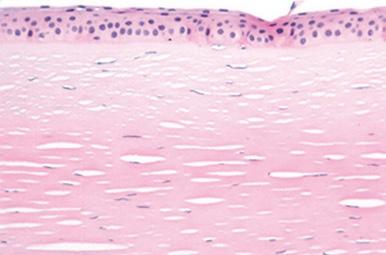

Figura 2. Linfoma epiteliotrópico en unión mucocutánea. Infiltración linfoide neoplásica en dermis superficial (flecha negra) y mostrando comportamiento epiteliotrópico (flecha blanca) (tinción hematoxilinaeosina, 30 x).

El estudio histopatológico por escisión de la trufa mostró hiperplasia epidérmica y una intensa infiltración dérmica superficial multifocal a difusa, conformada por células linfoides de tamaño medio, con anisocariosis moderada, escaso citoplasma y mitosis aisladas, observándose infiltración focal en la unión dermoepidérmica (epiteliotropismo) (Fig. 2). El diagnóstico presuntivo fue de linfoma epiteliotrópico. El estudio inmunohistoquímico evidenció una población linfoide CD3+, CD20-, fenotipo correspondiente a una población de linfocitos T, que confirmó el diagnóstico de linfoma epiteliotropo cutáneo asociado a fenotipo T (Fig. 3).

Figura 3. Linfoma epiteliotrópico en unión mucocutánea. Células neoplásicas de imagen anterior (Fig. 2) mostrando tinción positiva a CD3, infiltrando dermis superficial (flecha negra) y mostrando comportamiento epiteliotrópico (puntas de flecha negras) (tinción de linfocitos T mediante técnica inmunohistoquímica con anticuerpo anti-CD3 y contraste con hematoxilina, 30 x).